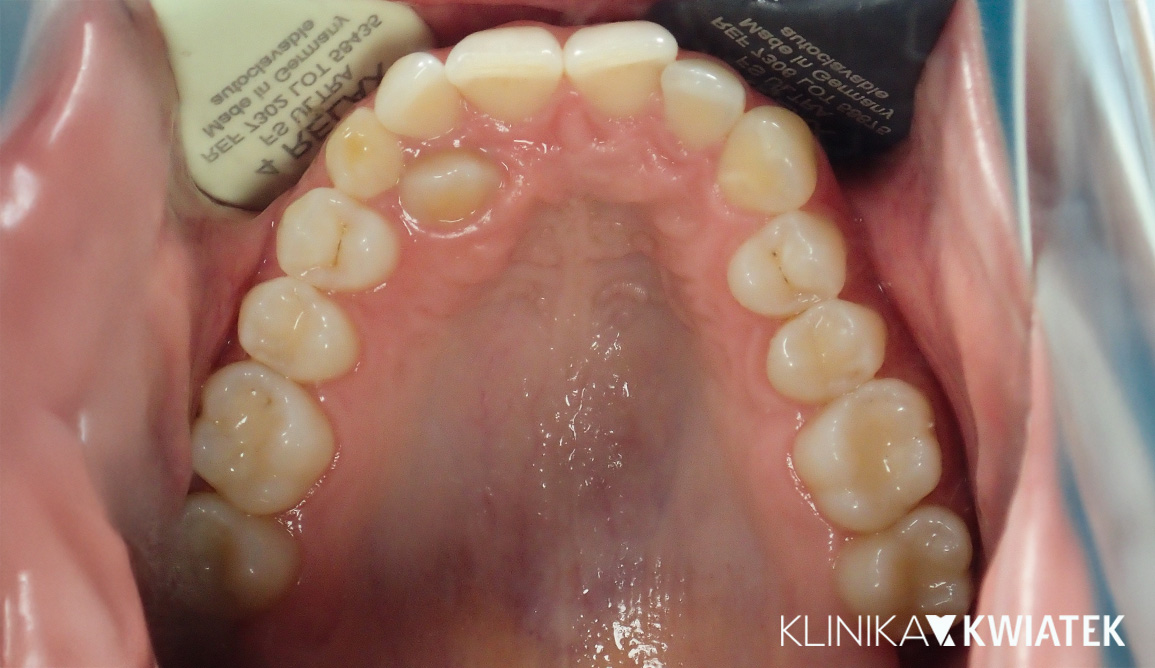

PRZED

PO

Zatrzymany kieł? Nowoczesna ortodoncja ma rozwiązanie!

27 letnia Pacjentka zgłosiła się do naszej kliniki z problemem wyrzynającego się nieprawidłowo kła górnego, przesuniętą linią pośrodkową i powiększonym nagryzem pionowym. Dzięki kompleksowej diagnostyce, leczeniu ortodontycznemu z zastosowaniem aparatów estetycznych i metalowych, wsparciu fizjoterapeutycznemu oraz regularnym higienizacjom udało się uzyskać prawidłową funkcję i estetykę uśmiechu. Efektem końcowym jest harmonijny zgryz, stabilne utrzymanie rezultatów dzięki retencji oraz piękny, zdrowy uśmiech.